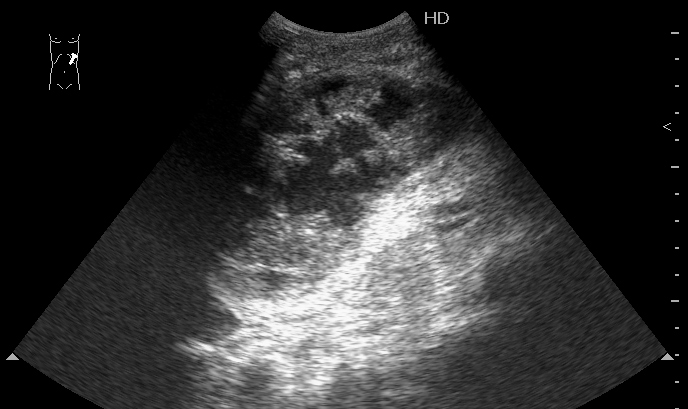

Мужчина 1952 г.р. поступил с болями в животе в БСМП. Длительное время страдал хроническим панкреатитом. Травму отрицает.

УЗИ селезенки, продольное сканирование

Мы вначале предпложили внутрикапсульный разрыв селезенки и ее разможжение, несмотря на отсутствие данных за травму (иногда наши пациенты имеют обыкновение её скрывать).

И ошиблись.

На секции - хронический панкреатит, псевдокиста селезенки. После вскрытия капсулы селезенки выделилась серая жидкость без примесей крови.

Механизм образования такой псевдокисты (?) мне лично непонятен, думаю обсудить это дело с университетскими анатомами.